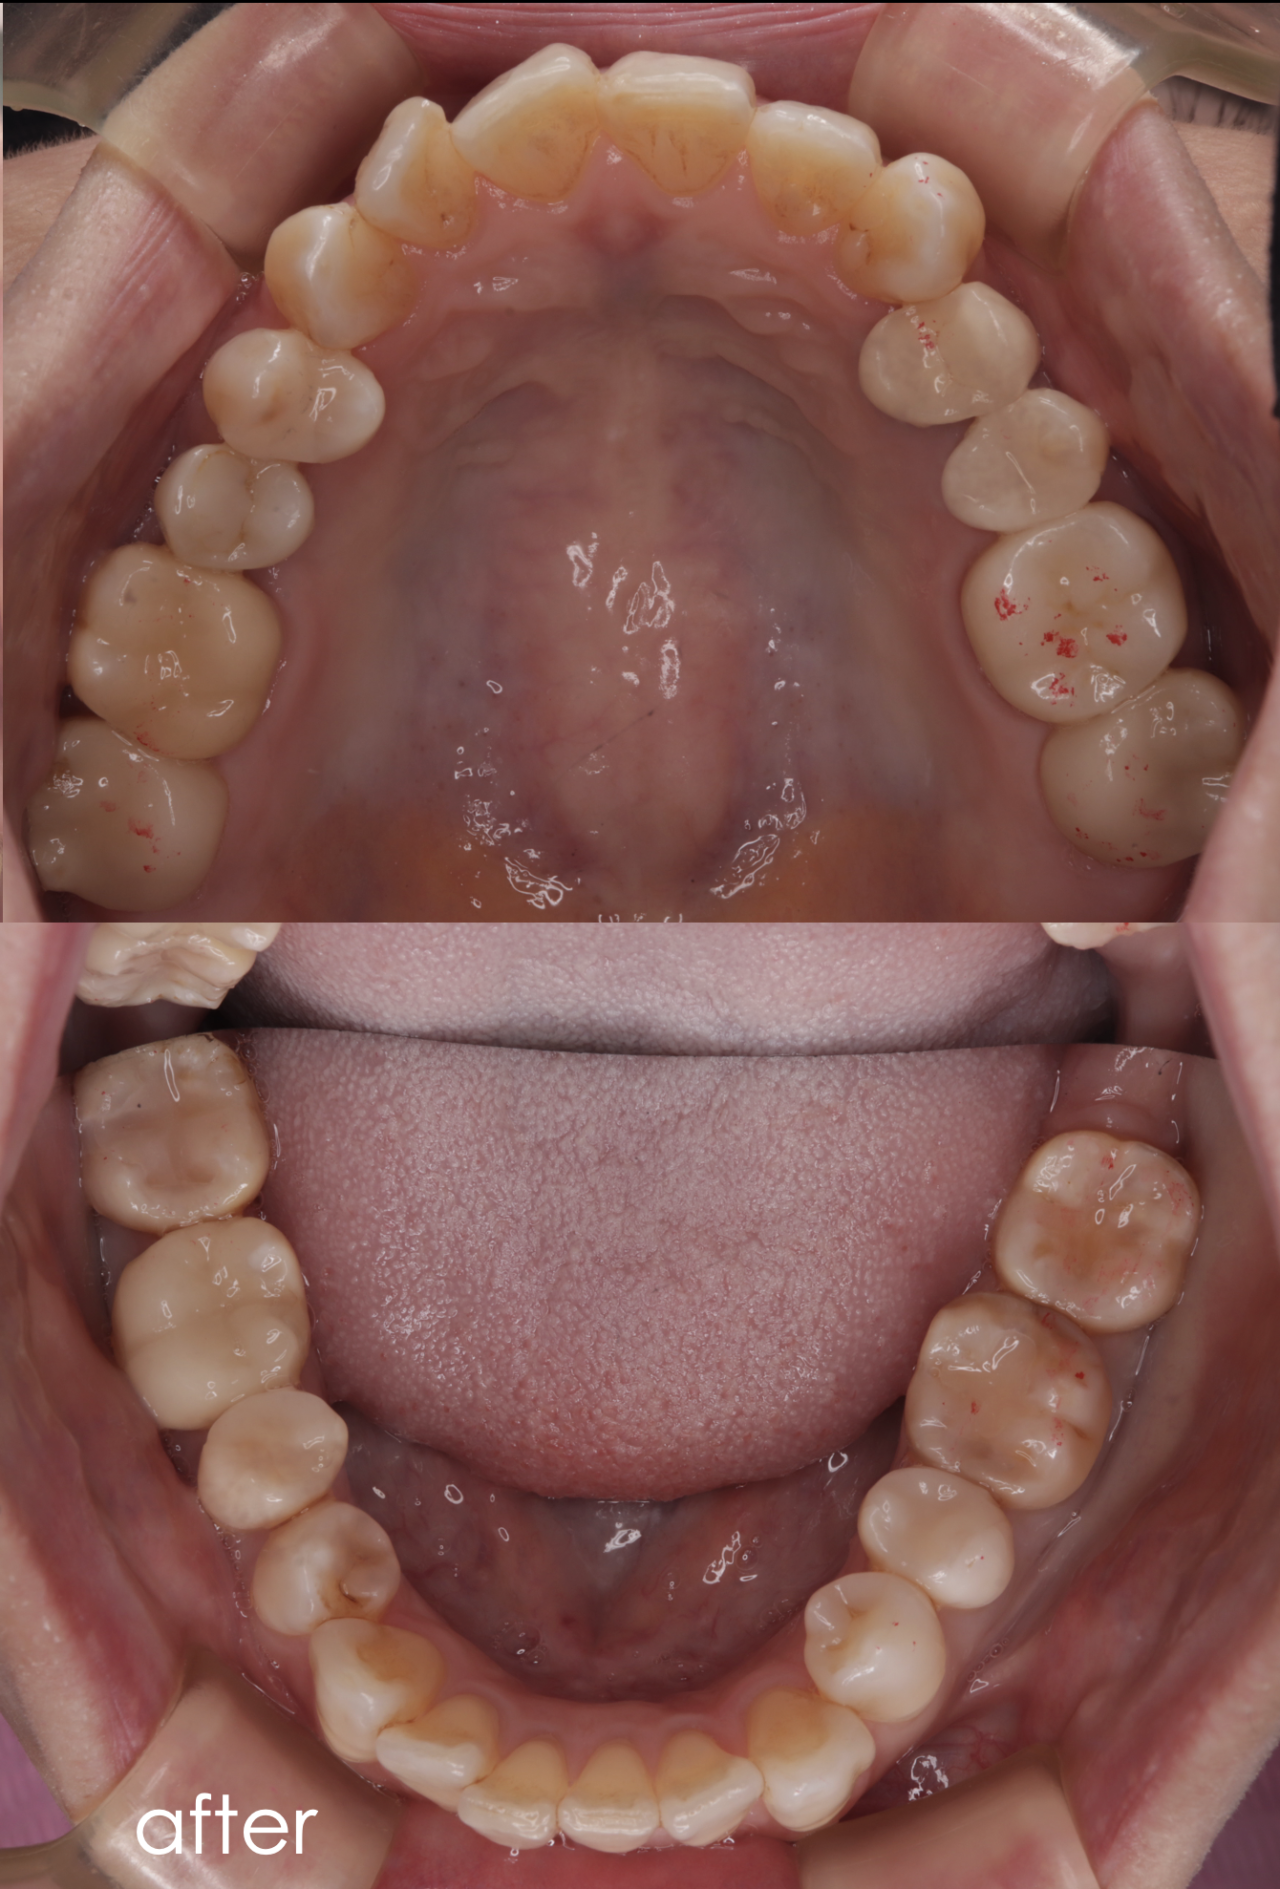

50代女性_左上根管治療予後不良_全体に治したい

before

after

| 年齢 | 50代 |

|---|---|

| 性別 | 女性 |

| 治療内容 | 左上奥歯の歯肉が腫れて痛い。他の歯科医院で根管治療を受けているが治療方針に不安があったため、当院を調べて来院されました。 |

| 治療期間・回数 | 約20回 1年4ヶ月 |

| 費用 | インプラント治療50万円、セラミック治療6万円〜10万円(税別) |